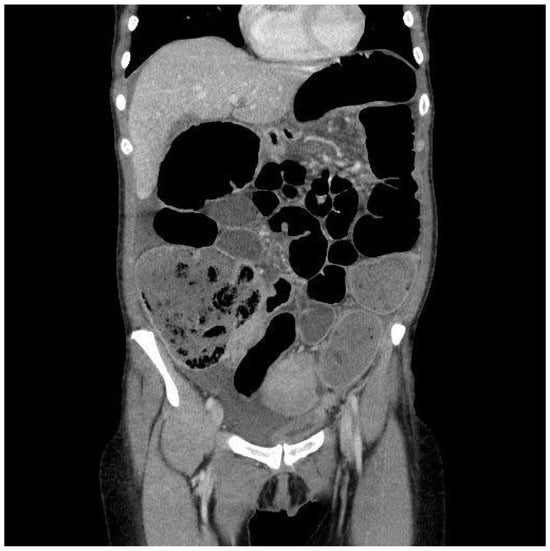

The first patient, a 48-year-old woman, came to the general Emergency Room in March 2023. She had been experiencing abdominal pain, distention, and intestinal obstruction a few days before her visit. Importantly, she exhibited no signs of fever and had no notable medical history. A CT scan showed an enlarged right adnex with multiple fluid-filled cysts (Figure 1). The left side of the uterus appeared thickened and was in continuity with the left bladder wall (Figure 2). Moreover, the colonic wall displayed thickening and hyperemia. The abdominopelvic area contained heterogeneous material with fluid pockets and signs of peritoneal fluid effusion. Consequently, the patient was referred for a gynecological evaluation. Clinical findings indicated abdominal distension accompanied by pain upon palpation. A bimanual examination uncovered indeterminate solid tissue. The ultrasound revealed a thin, linear endometrium and an enlarged right ovary, while the left ovary was significantly adhered to the sigmoid colon. Laboratory results showed an elevated white blood cell count (15.02 × 103/µL) and a higher C-reactive protein level (CRP 40.49 mg/L). Due to the high suspicion of gynecological malignancy, the patient underwent surgical procedures including laparotomic hysterectomy, bilateral tubo-oophorectomy, sigmoid resection with ileostomy, removal of the round ligament, omentectomy, appendectomy, and peritoneal biopsies. Intraoperative observations noted substantial adhesions involving the uterus, ovaries, and the sigmoid–rectal tract, along with mild ascitic effusion. An intraoperative histological assessment identified Actinomyces colonies. Despite this, the extensive disease burden suggested that demolitive surgery was warranted. Histological examination of the specimen diagnosed pelvic inflammatory disease featuring a tubo-ovarian abscess, revealing necrotic tissue with inflammatory characteristics, significant inflammation, and Actinomyces colonies mainly in the round ligament and right ovary. As a complication, the patient required a bilateral pyelostomy because of a left ureteral fistula linked to pelvic effusion stemming from past inflammation and vesicoureteral reflux. Nine months later, she underwent ano–rectal fistula repair. She received three months of antibiotic therapy with Amoxicillin and Doxycycline, followed by an additional eleven months of Amoxicillin, depending on complications after surgery. Fourteen months post-initial procedure, an X-ray with barium enema/CT scan was performed, indicating significant remission of complications. Currently, she is asymptomatic and continues to attend follow-up appointments monitoring.

Figure 2.

Frontal CT scan. In this case, the main aspect is diffuse and consistent bowel dilatation, which can be a common aspect in stenotizing cancer infiltration. However, for a more detailed look, it is possible to appreciate bowel thickened walls and phlogistic effusion, which can make clinicians suspect an inflammatory disease.

Considering the imaging findings, the pelvic masses observed in both cases presented characteristics indicative of a potential malignancy. The masses were primarily associated with adnexal structures, exhibiting either cystic or solid contents and forming adhesions with adjacent anatomical entities. Although the ultrasound examination may have yielded nonspecific results, the CT scan also displayed images suggestive of gynecological malignancy. It would be improbable to suspect a benign pathology based solely on clinical examination and imaging findings, corroborating the existing literature.